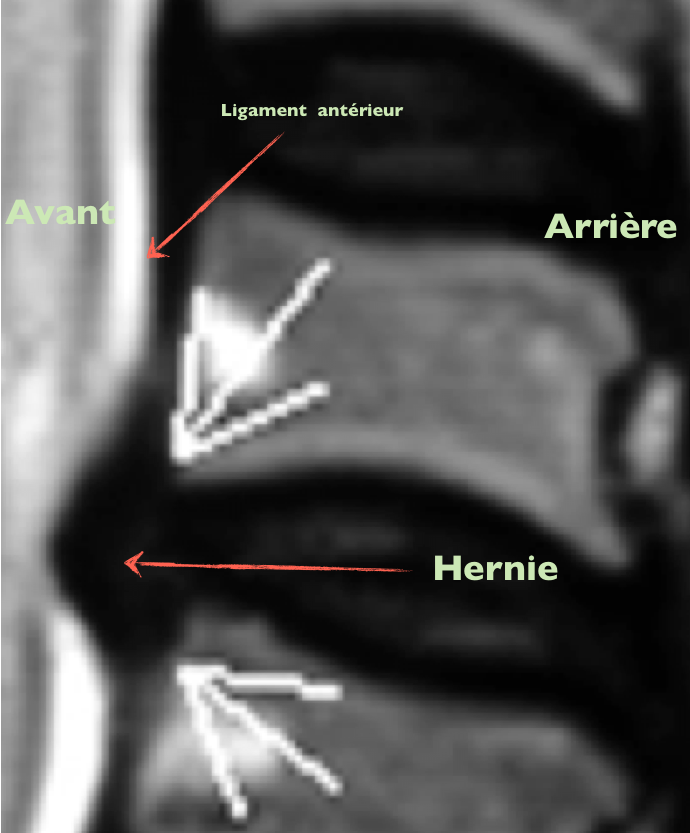

Hernie antérieure Publié 4 octobre 2013 à 690 × 833 dans Les disques et vos douleurs ← Précédent Suivant → J’aime chargement… Poster un commentaire ou un rétrolien.